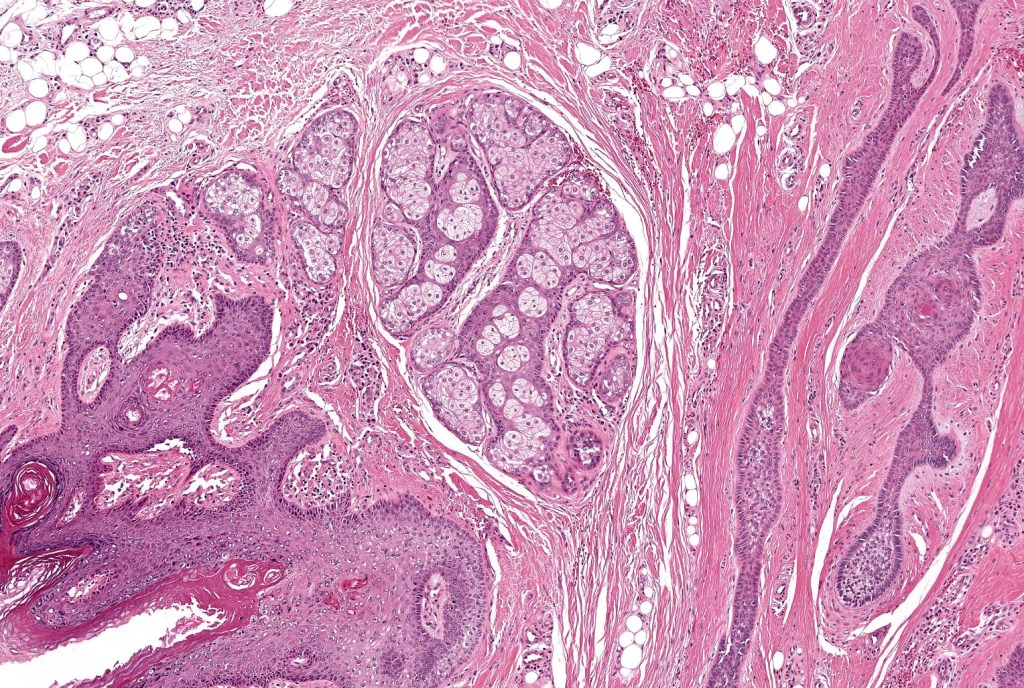

•Circumscribed dermal nodule with a characteristic silhouette

•An infundibular cyst is surrounded by laminated dermal collagen, elastic fibers, blood vessels, adipocytes & spindle cells separated from the adjacent dermis by a retraction artifact

•The cyst contains keratinous debris, and its wall shows conspicuous sebaceous & sometimes hair follicular elements are also evident